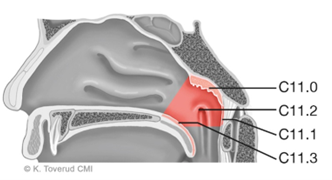

For inntegning av lymfeknuteregioner (Nivåer I – Xb, figur 9.1) mtp. elektiv bestråling, henvises det til Gregoire et al. (2014), Biau et al. (2019) og DAHANCA (2021).